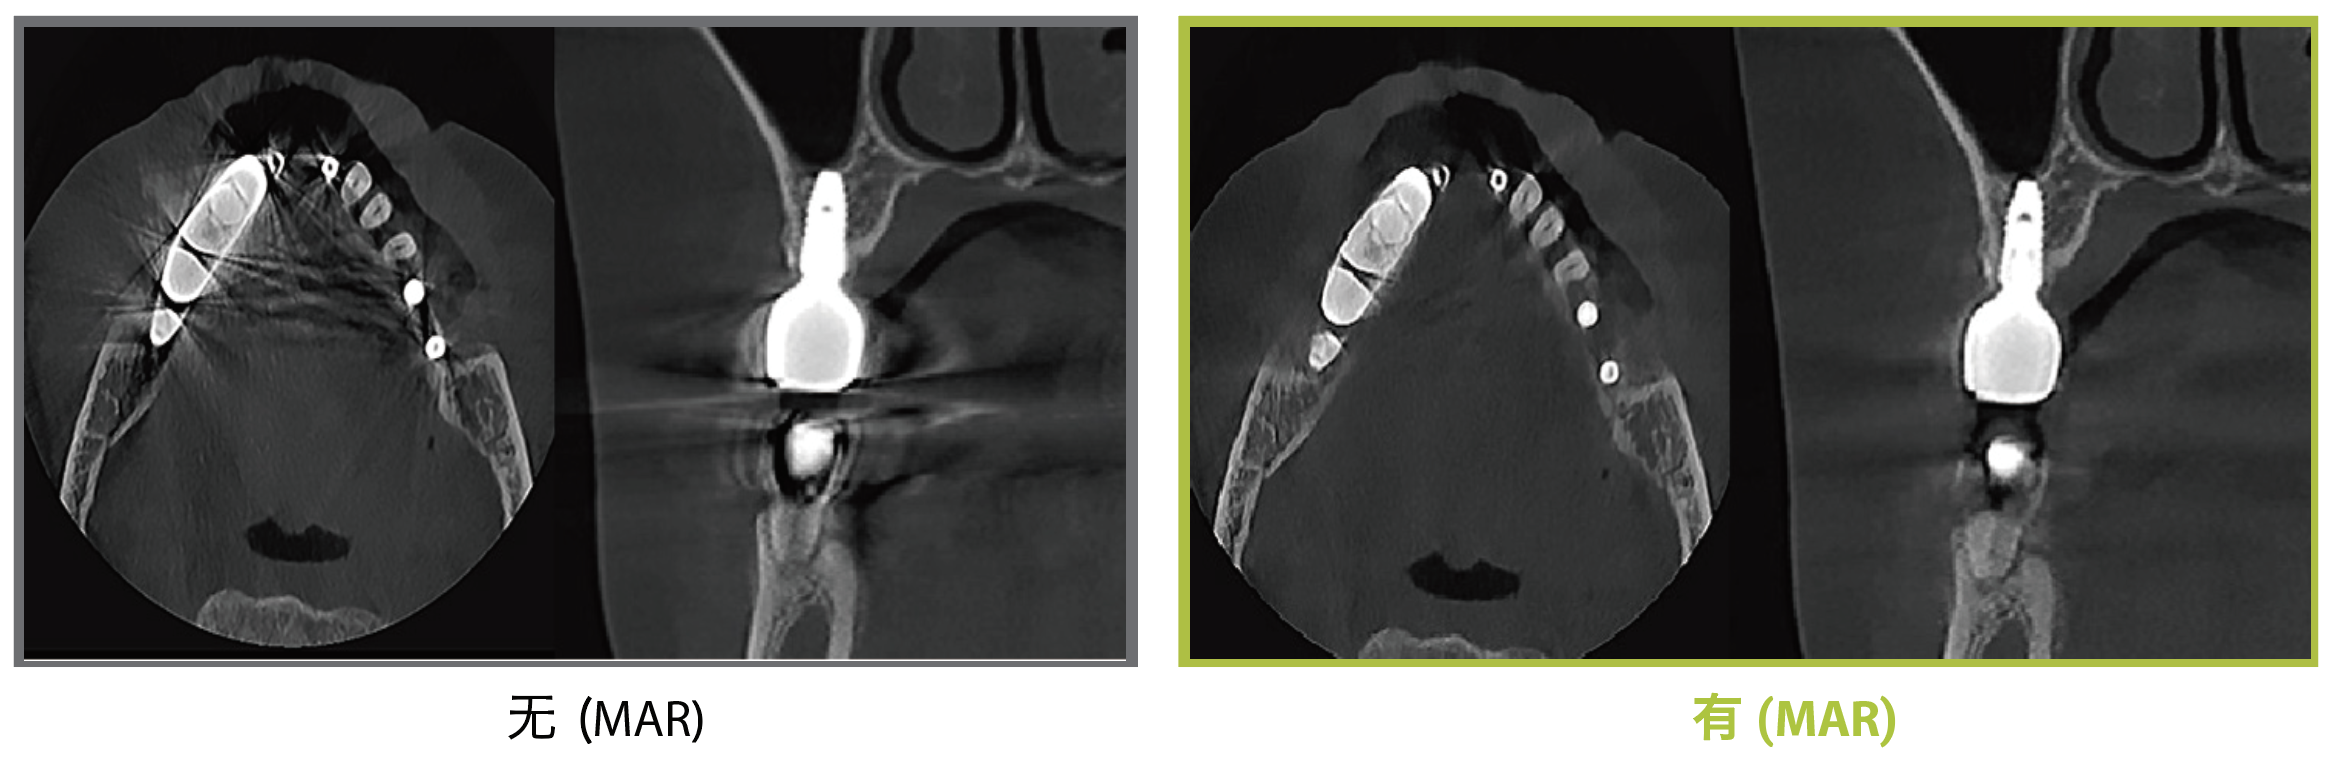

? 突破性金屬減影算法,強(qiáng)化后的金屬減影效果提升

bright MAR金屬減影算法

通過實(shí)時(shí)比較的Dentium MAR技術(shù),自動(dòng)減少由植入物、填充物或修復(fù)體引起的金屬偽影。這有助于確認(rèn)并降低誤診的風(fēng)險(xiǎn)。